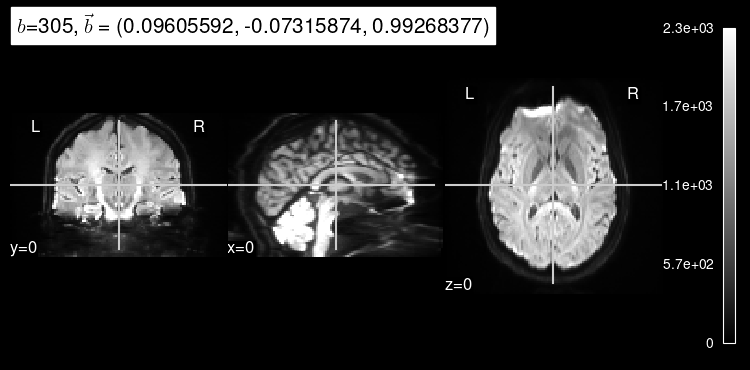

plot_dwi(np.squeeze(data_test[0]), dmri_dataset.affine, gradient=data_test[1]);